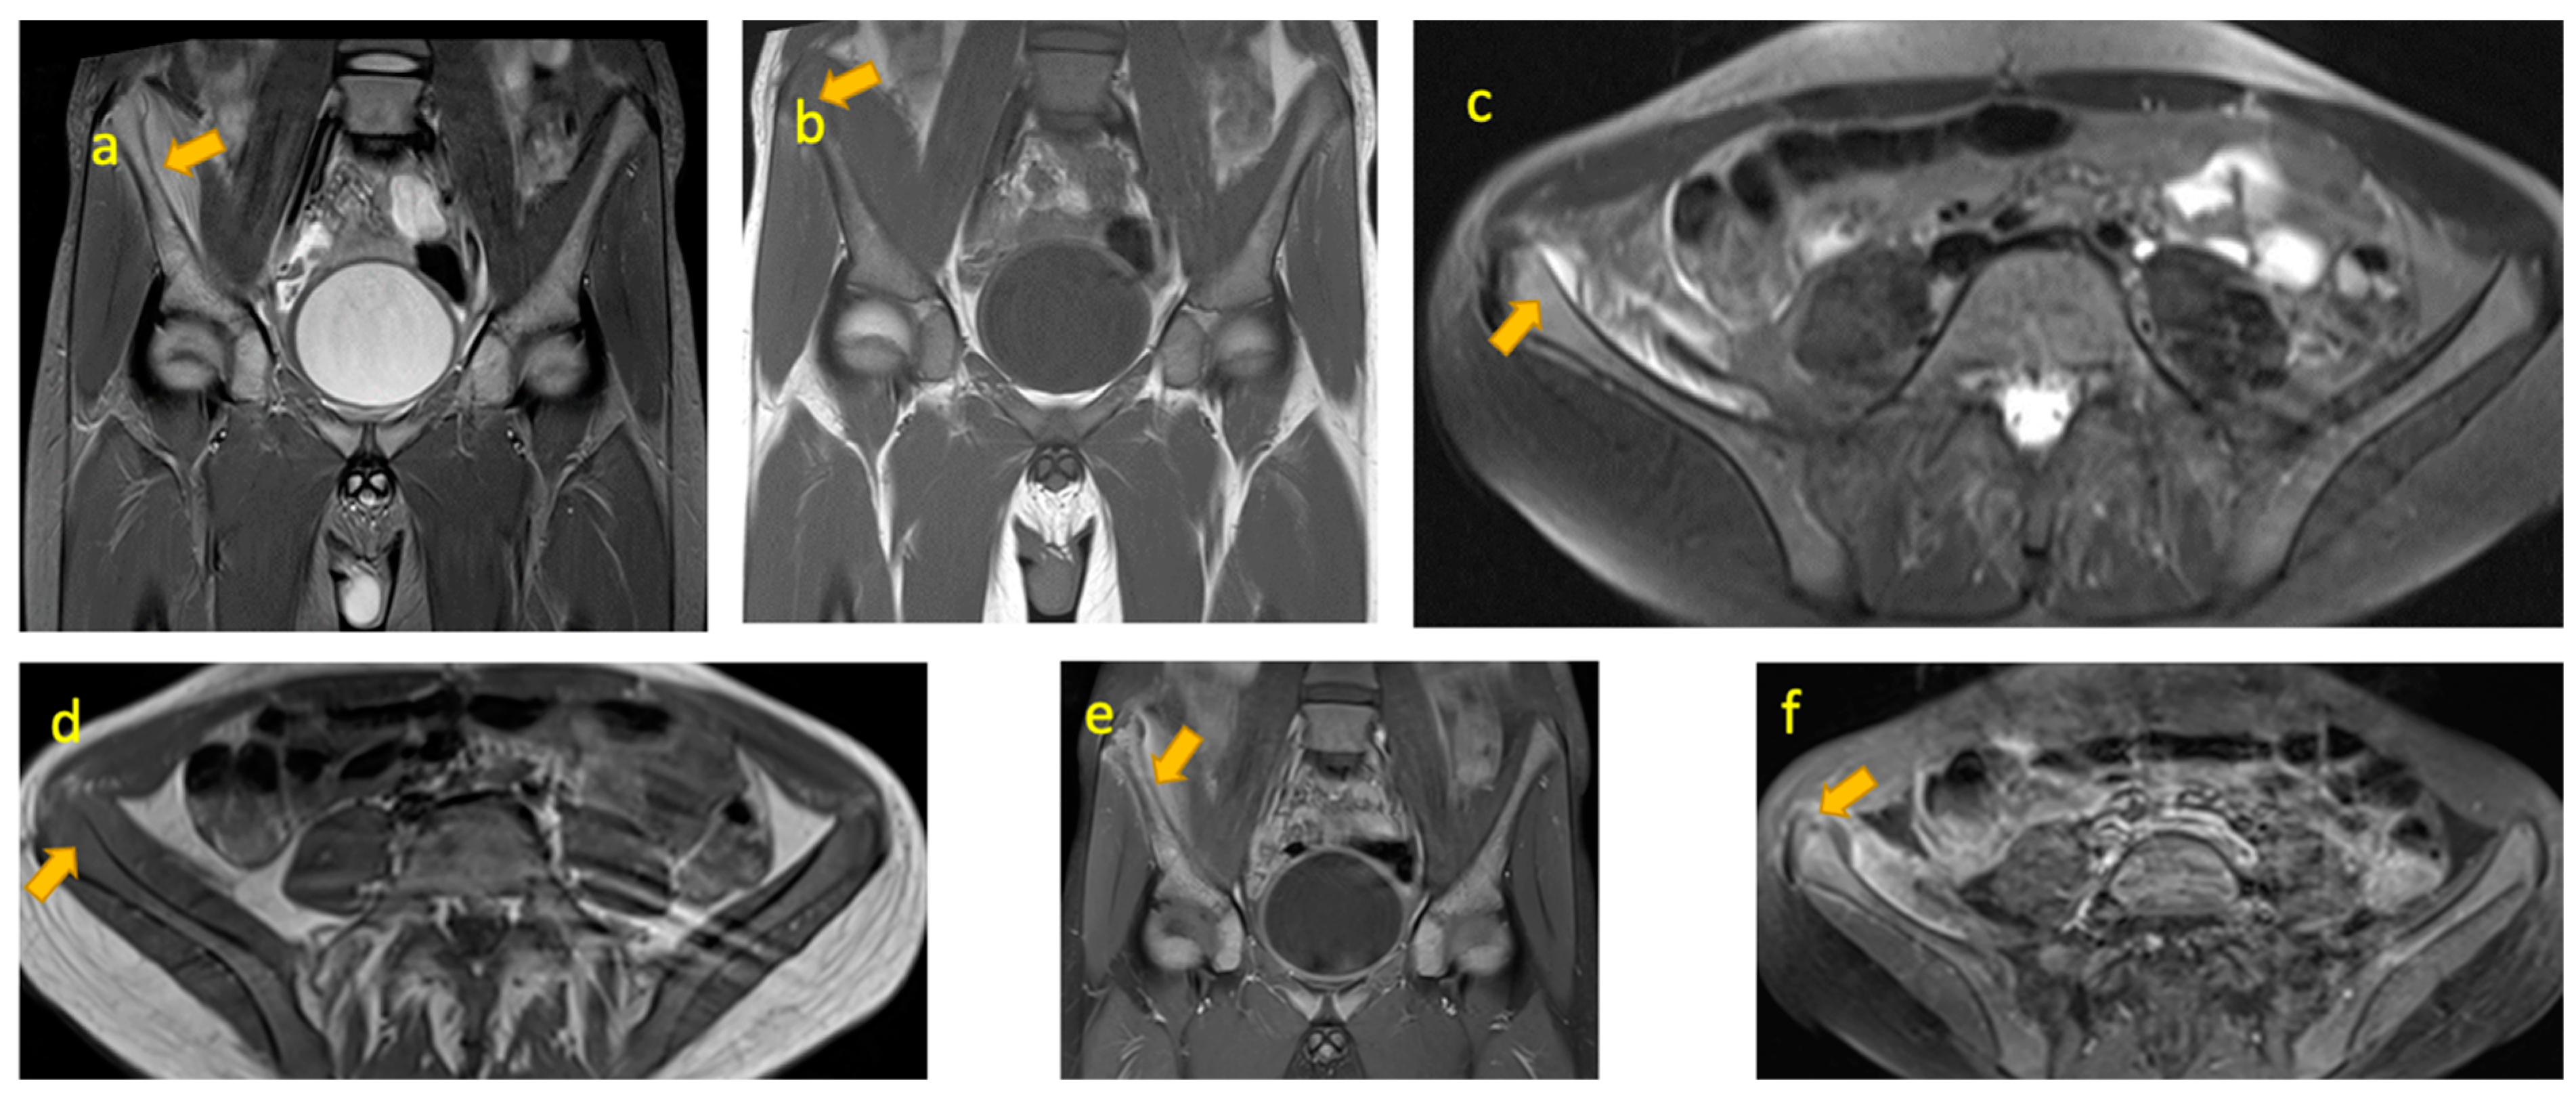

5. Juvenile Idiopathic Arthritis of the Hip

7. Crystal Arthritis of the Hip

8. Osteomyelitis Iliac Crest

11. Leukaemia

13. Septic Arthritis of the Sacroiliac Joint

16. Stress Fracture of Sacral Ala